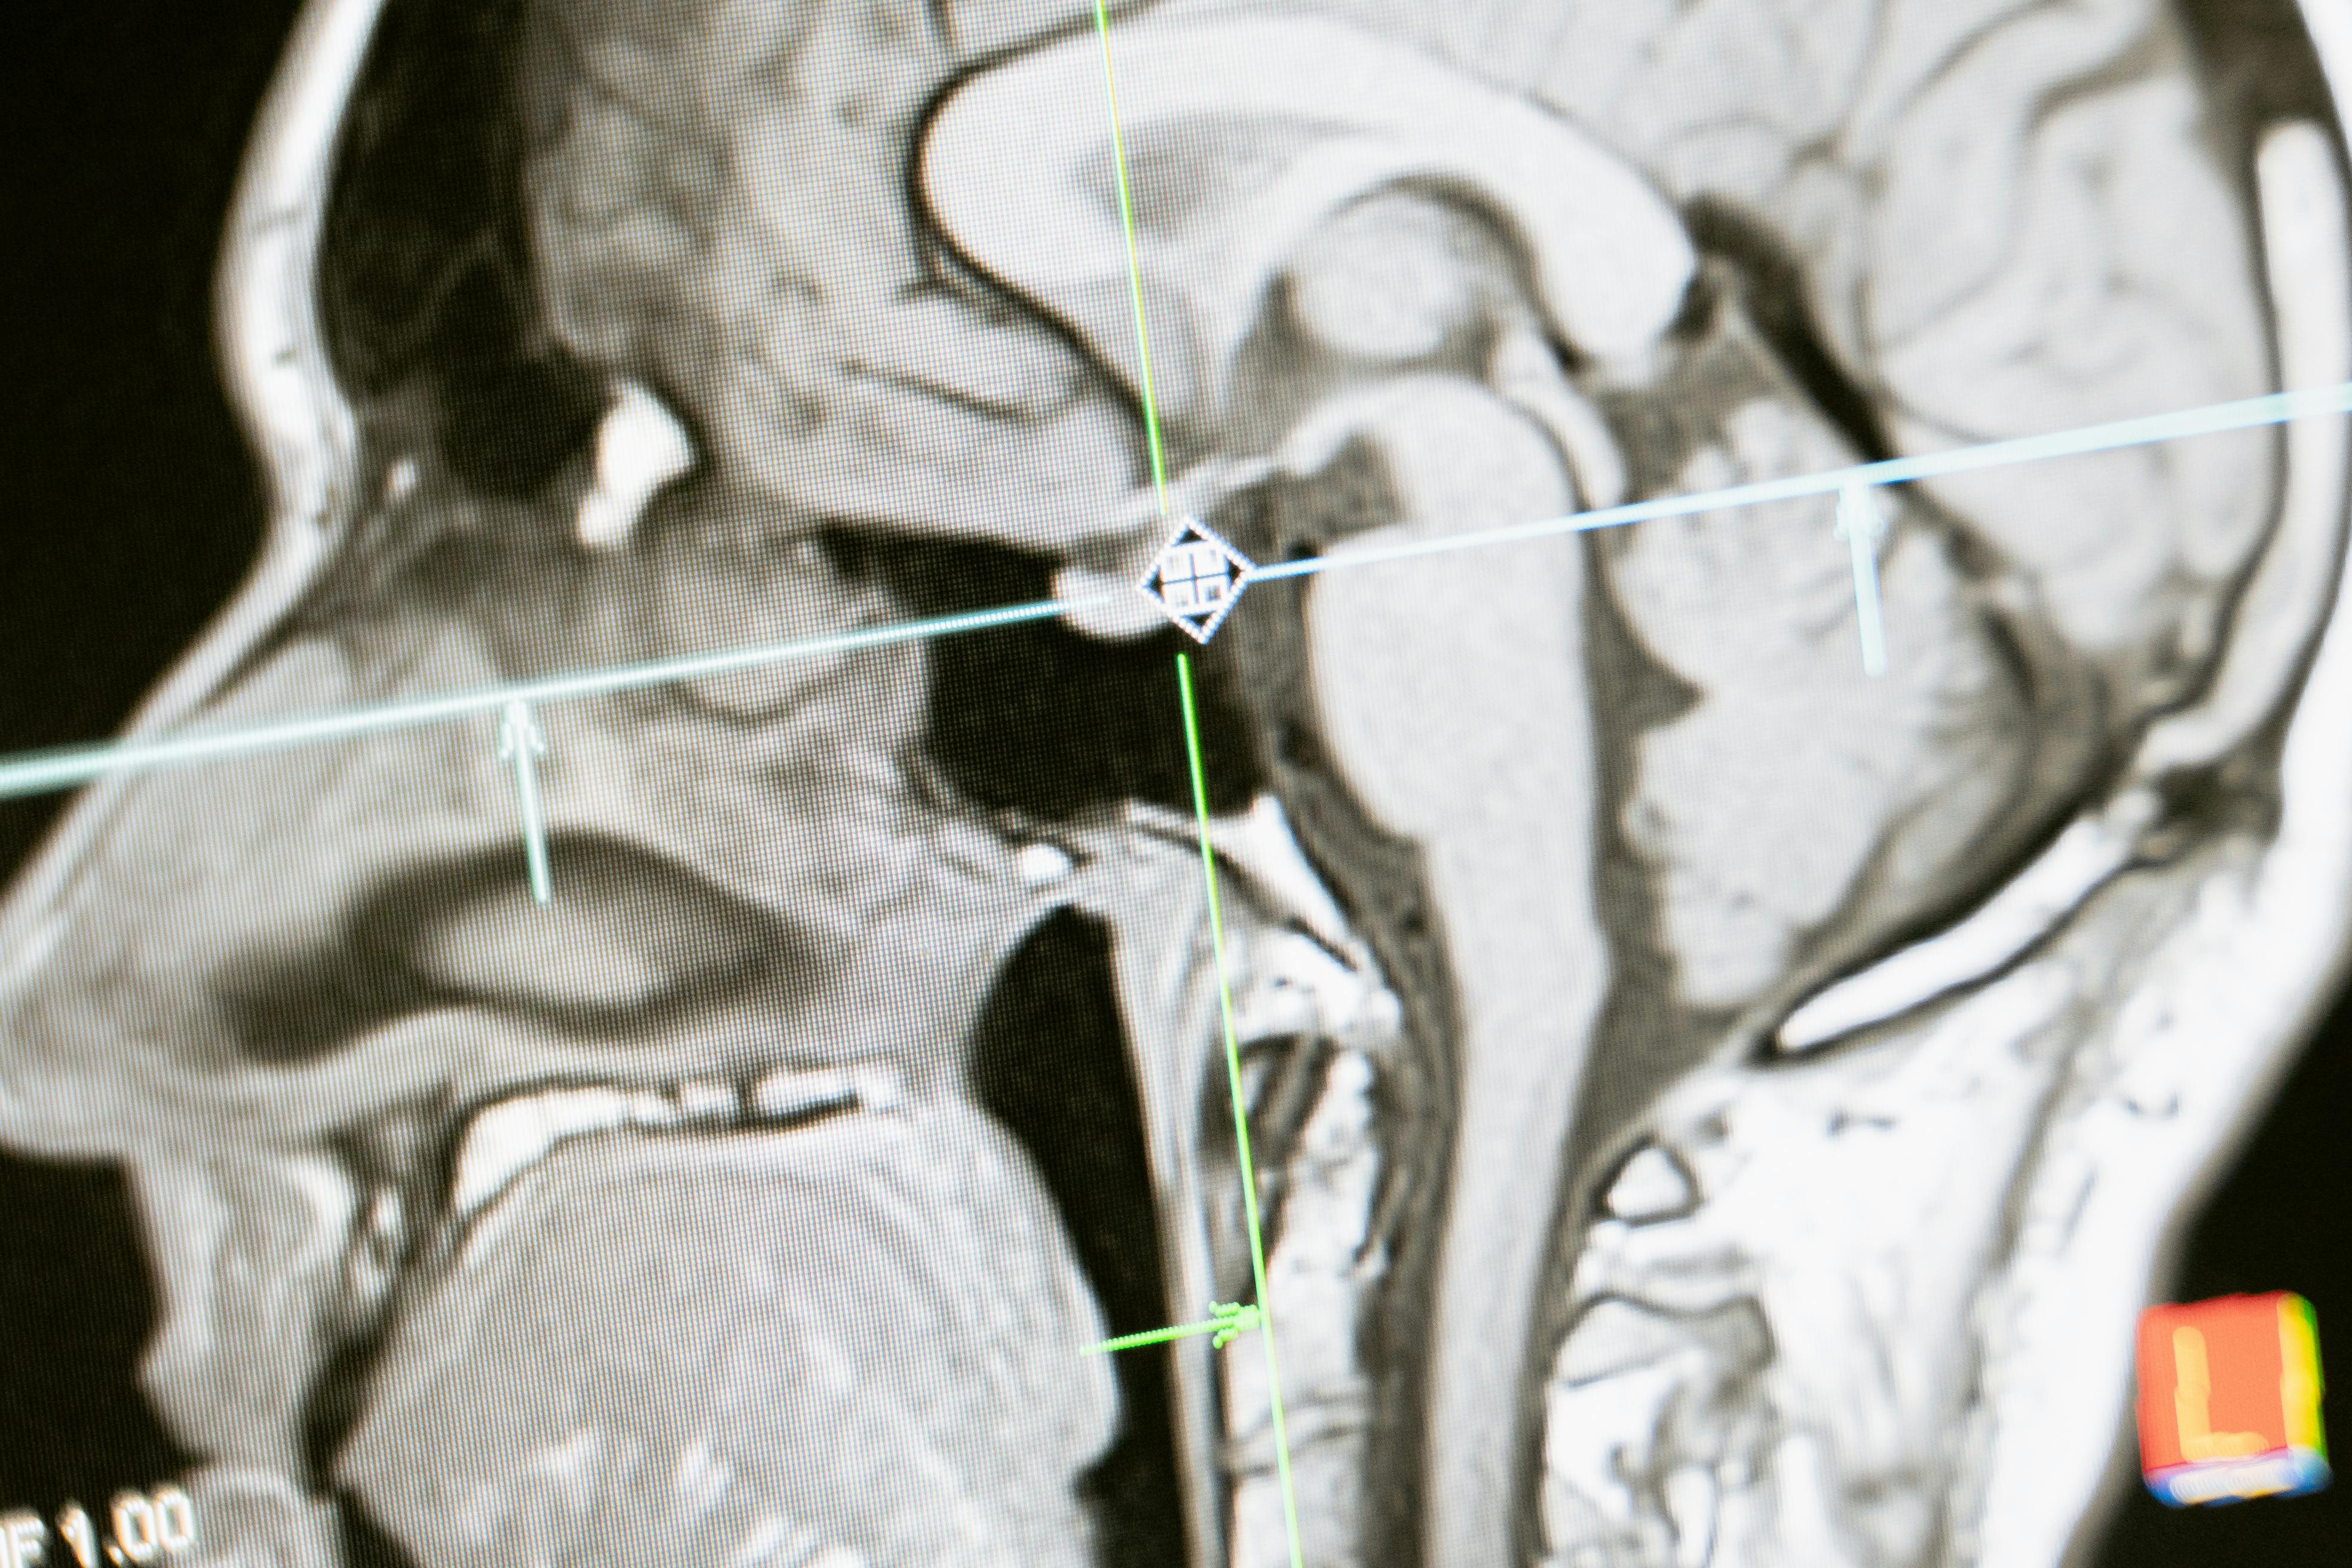

neuro scan.